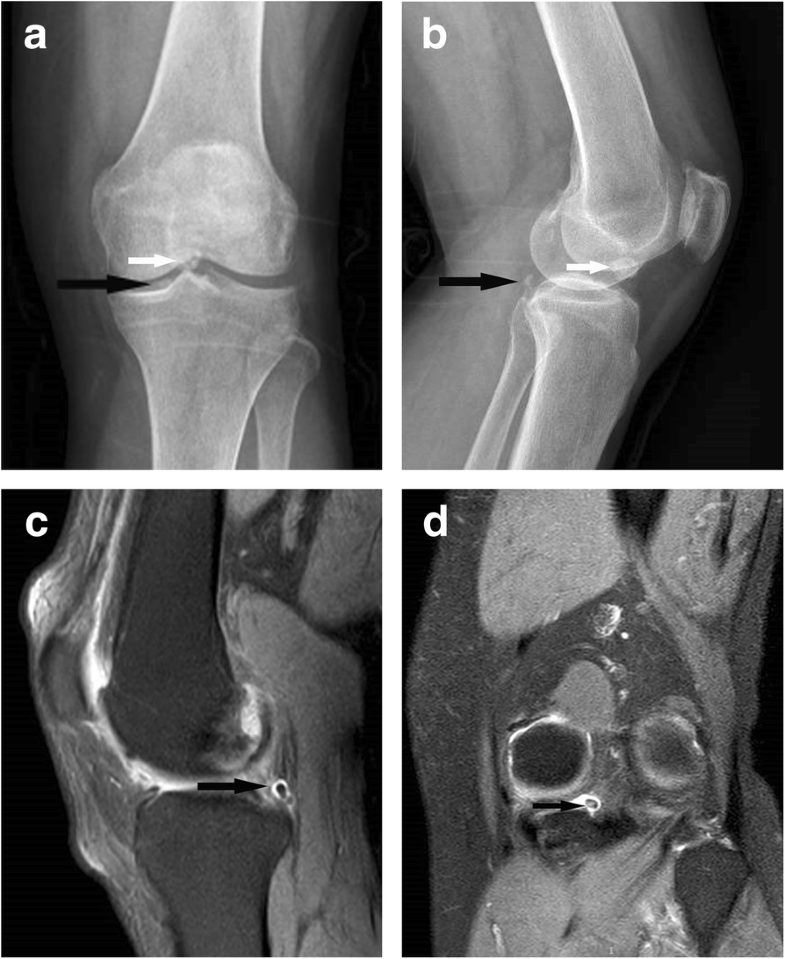

Radiographs and arthroscopy of osteoarthritis. A and B are Arthroscopic Knee Surgery For Loose Bodies The purpose of the present study was to explore the efficacy of arthroscopic loose body removal for knee osteoarthritis (koa). Loose bodies are another name for free floating pieces of debris in the joint. The aim of loose body removal surgery is to remove the cartilage or bone that has broken free during injuries and has caused the joints to. Arthroscopic Knee Surgery For Loose Bodies.